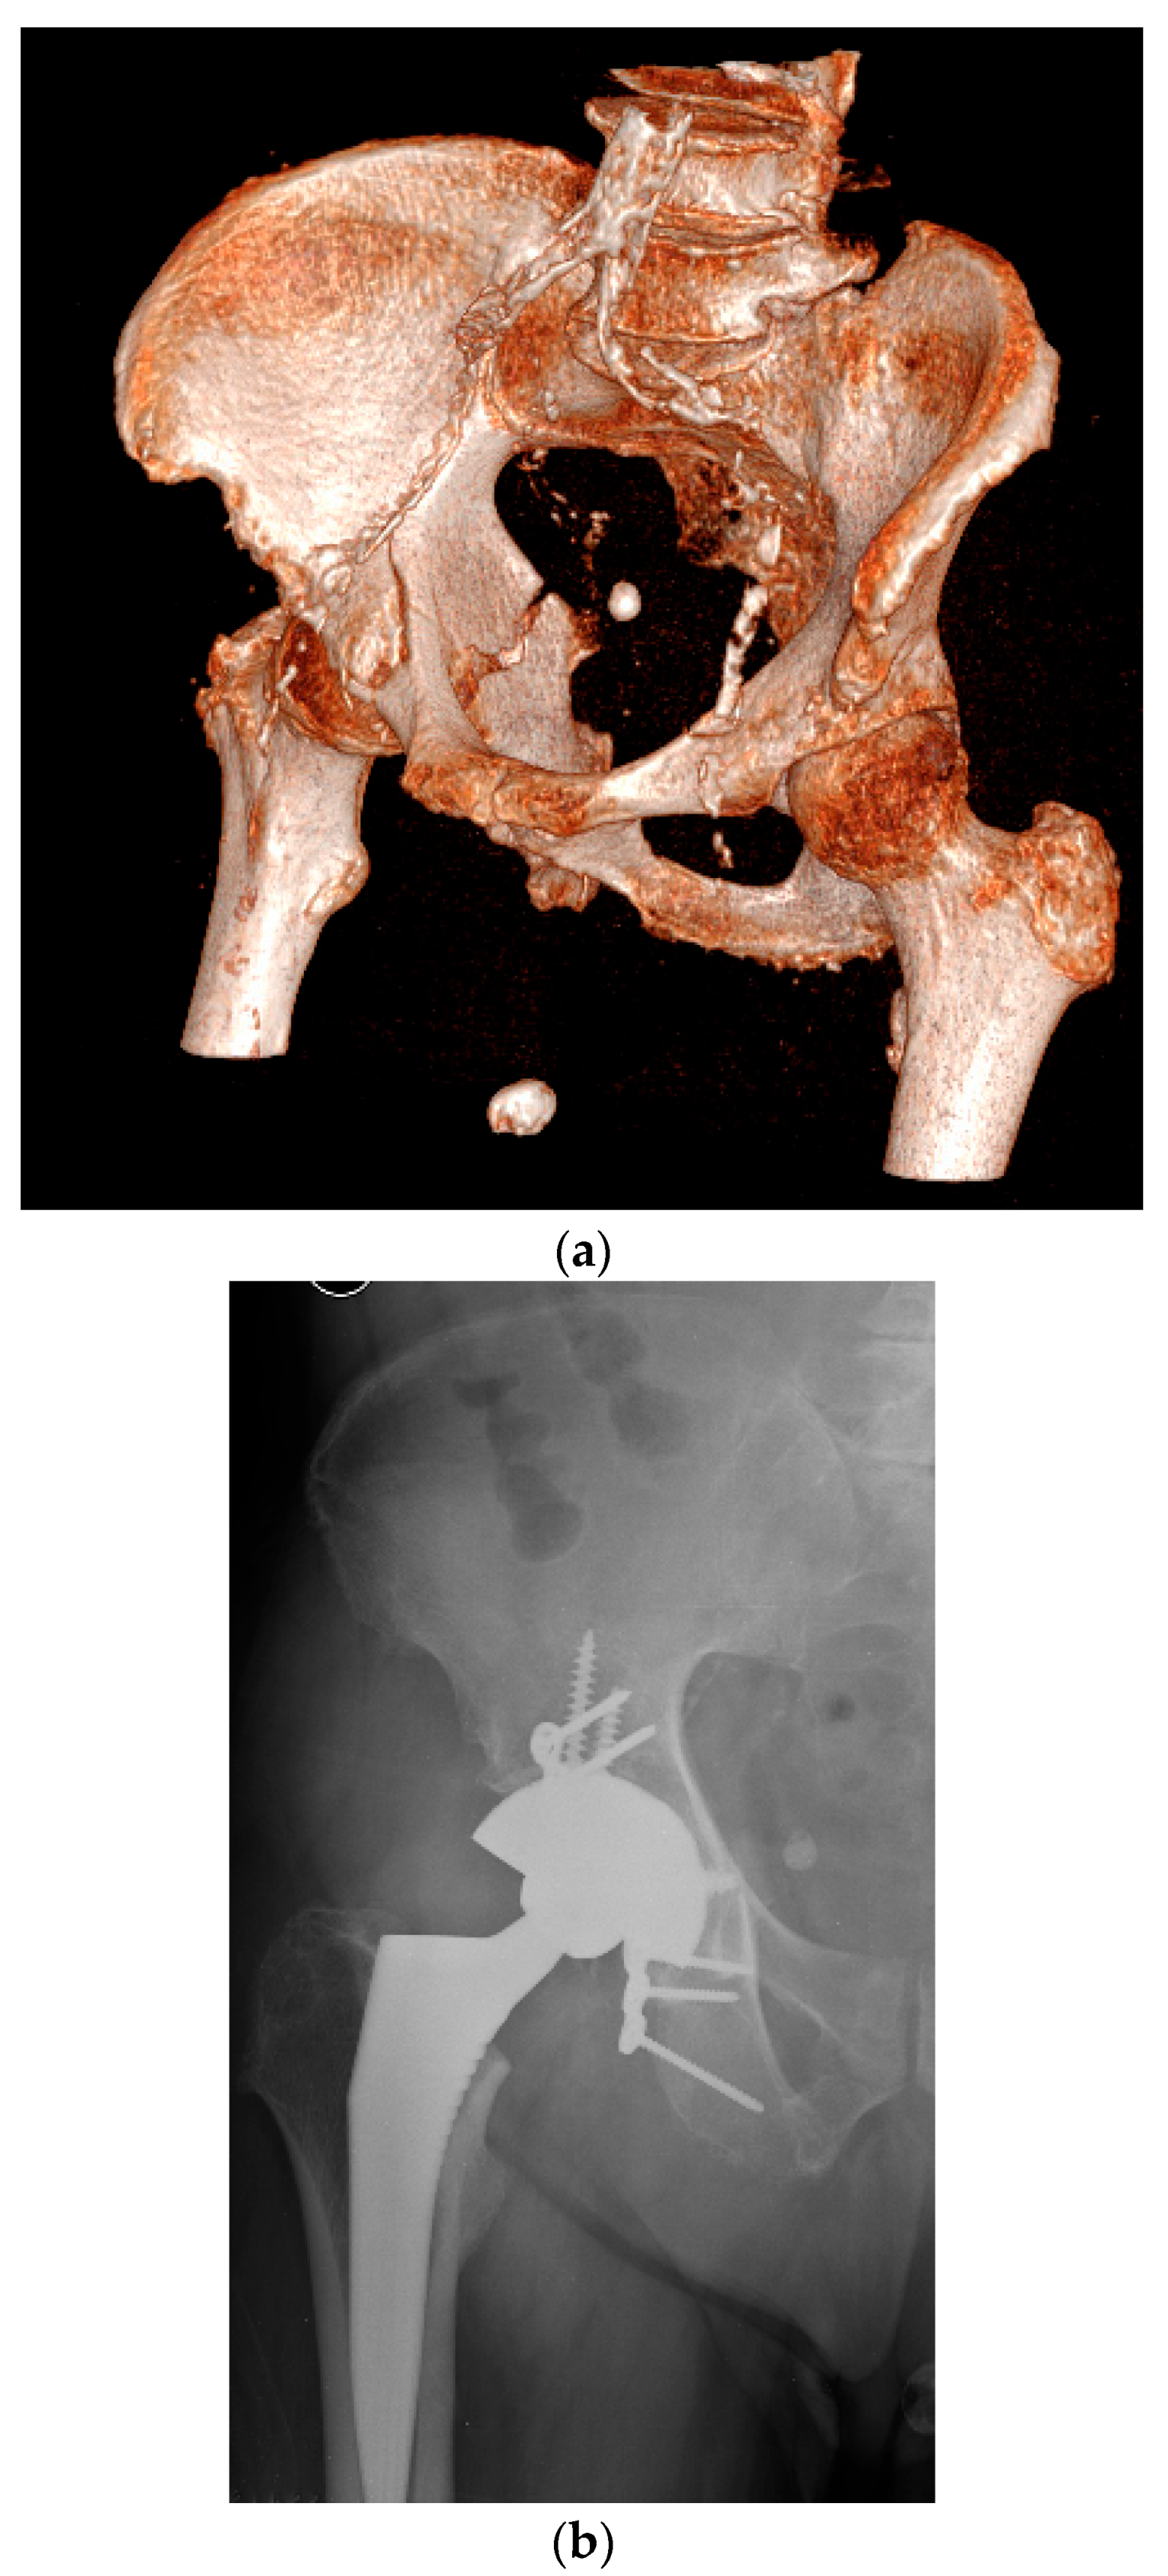

4.3. Acute THA in Acetabular Fractures

- Delgadillo, C.A.; Pesantez, R. Fix and replace technique in elderly acetabular fractures. J. Musculoskelet. Surg. Res. 2023, 7, 252–258. [Google Scholar] [CrossRef]